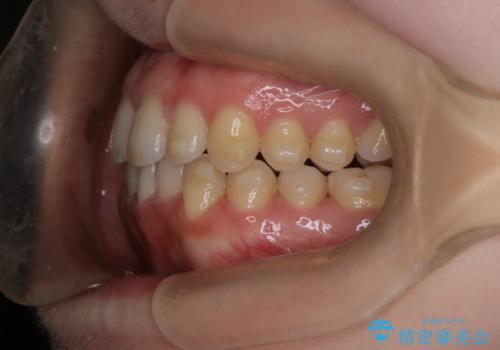

- 前歯の凸凹を主訴に来院された患者様です

骨格性の下顎前突傾向もあったため、臼歯関係の遠心移動も行うことで綺麗な仕上がりで矯正を終了することができました。

遠心移動を行うことで期間はかかりましたが、良い状態で仕上がっています。